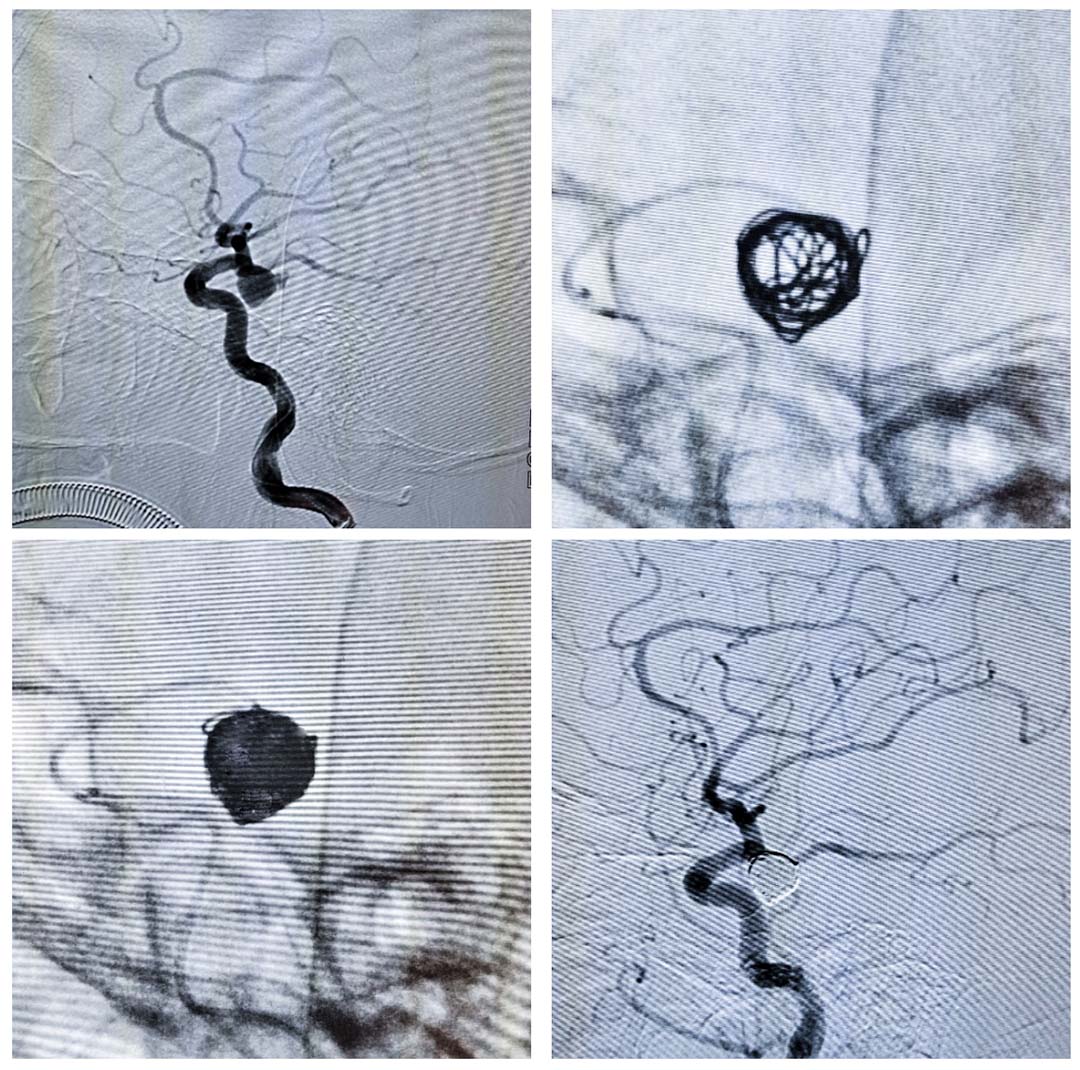

123日晚,宣汉县人民医院在抓好疫情防控工作的同时不影响危重症患者的生命救治,医务人员身着防护服,全力为一名脑血管动脉瘤破裂出血的急诊患者打通生命通道血管介入科过硬的专业能力成功使转危为安

在疫情当下宣汉县人民医院展现“生命至上”的价值追求,温暖人心,为宣汉人民的健康提供了一道“保护锁”。这正是县人民医院在防控工作常态化下始终坚持疫情防控和日常诊疗工作两手抓、两手硬的高标准体现,也是医院患者至上”服务理念的完美诠释。